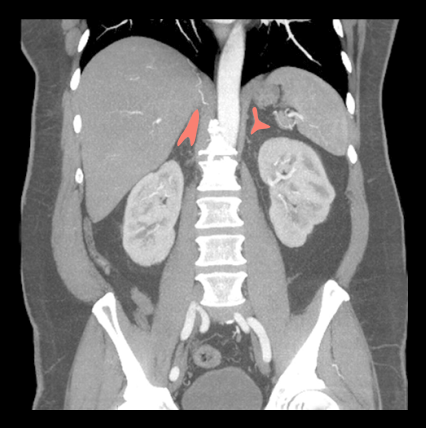

CT adrenal protocol helps to characterize masses in the adrenal glands. This study has multiple pre and post contrast phases that are used to identify contrast washout of masses.

Usually, there are three steps in the scan: pre-contrast, venous and delay.

- Plan all three steps to cover from the dome of the diaphragm to iliac crest.

A qualified Radiologist must calculate the Hounsfield unit (HU) values of adrenal lesions for all three phases to identify the contrast washout.